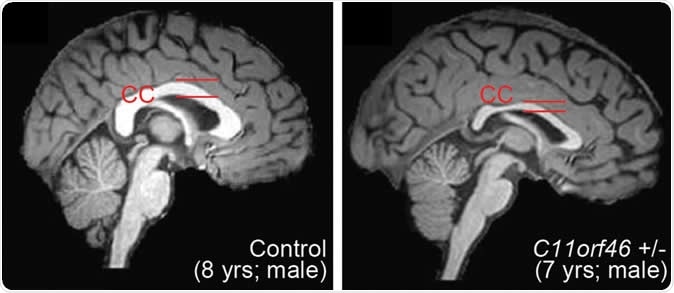

The gene they corrected is called C11orf46 and is crucial for controlling the development of the brain. It is responsible for the production of a nuclear protein that regulates certain important proteins that are capable of directing the newly forming long nerve fibers growing out of the developing nerve cells in the right orientation. These direction-sensing proteins help the white matter fibers to bundle together and form the large nerve trunk that traverses the space between the two hemispheres. This is the corpus callosum, and when it is improperly formed, the individual may be disabled, develop autism or another developmental disorder of the brain. Defects in the C11orf46 gene are linked to hypoplasia or poor development of the corpus callosum.

Healthy human brain (left) and brain with WAGR syndrome, in which the corpus callosum is thinner and misformed. Image Credit: Nature Communications

When this gene was knocked down, the projections of axons from one cerebral hemisphere to the other were disrupted. At the same time, multiple genes that code for certain essential events that regulate the development of nerve fibers are overexpressed in these cells. One of these is the Semaphorin 6a gene. This is normalized via epigenetic editing in the present study, producing normalization of the gene expression and restoring normal connectivity in the corpus callosum.